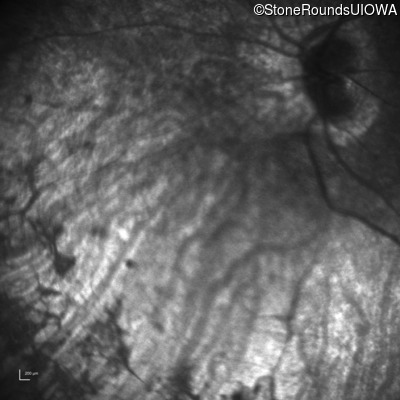

Age at visit:

30 years

OD

OS

Light Perception

OCT Stack

33 years

SECORD

RPGRIP1

His631Arg CAC>CGC

Pro237 del1ccA

AR